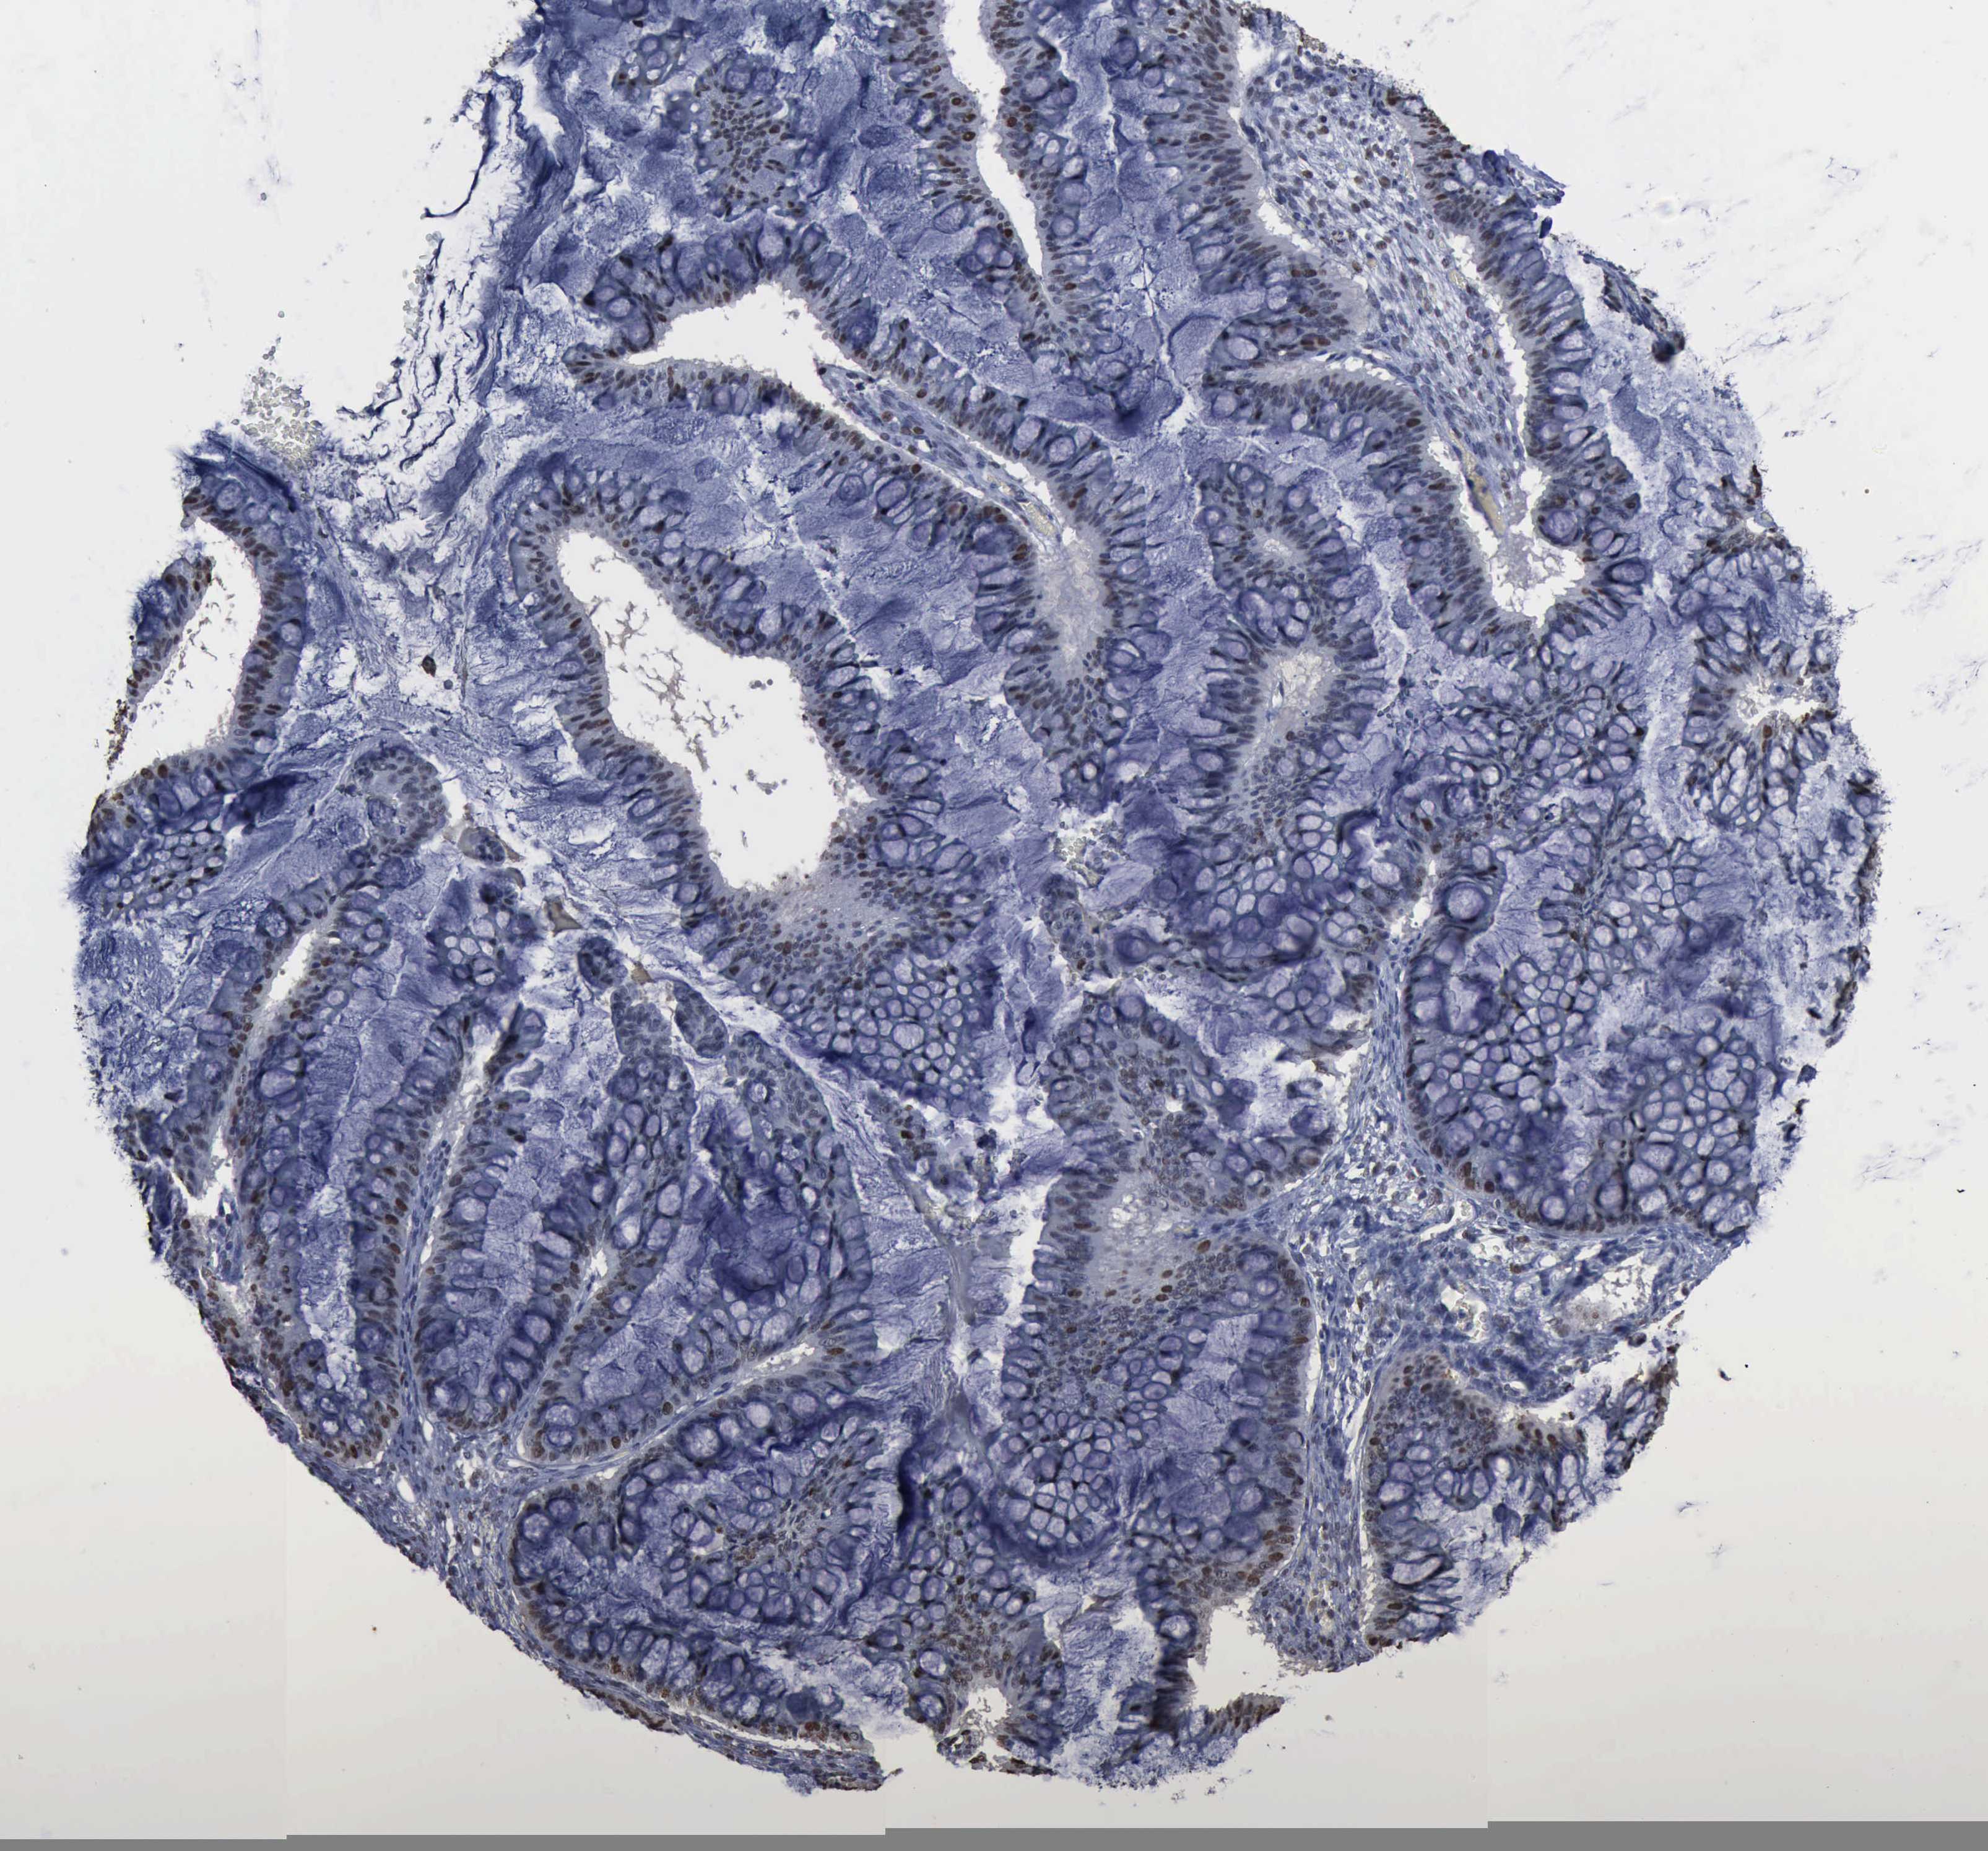

OVARIAN CANCER - Protein expressioni

A mouse-over function shows sample information and annotation data. Click on an image to view it in a full screen mode. Samples can be filtered based on level of antibody staining by selecting one or several of the following categories: high, medium, low and not detected. The assay and annotation is described here.

Note that samples used for immunohistochemistry by the Human Protein Atlas do not correspond to samples in the TCGA dataset.

Antibody stainingi

Antibody staining in the annotated cell types in the current human tissue is reported as not detected, low, medium, or high, based on conventional immunohistochemistry profiling in selected tissues. This score is based on the combination of the staining intensity and fraction of stained cells.

Each image is clickable and will lead to virtual microscopy that enables deeper exploration of all samples and also displays staining intensity scores, fraction scores and subcellular localization as well as patient and tissue information for each sample.

Carcinoma, endometroid